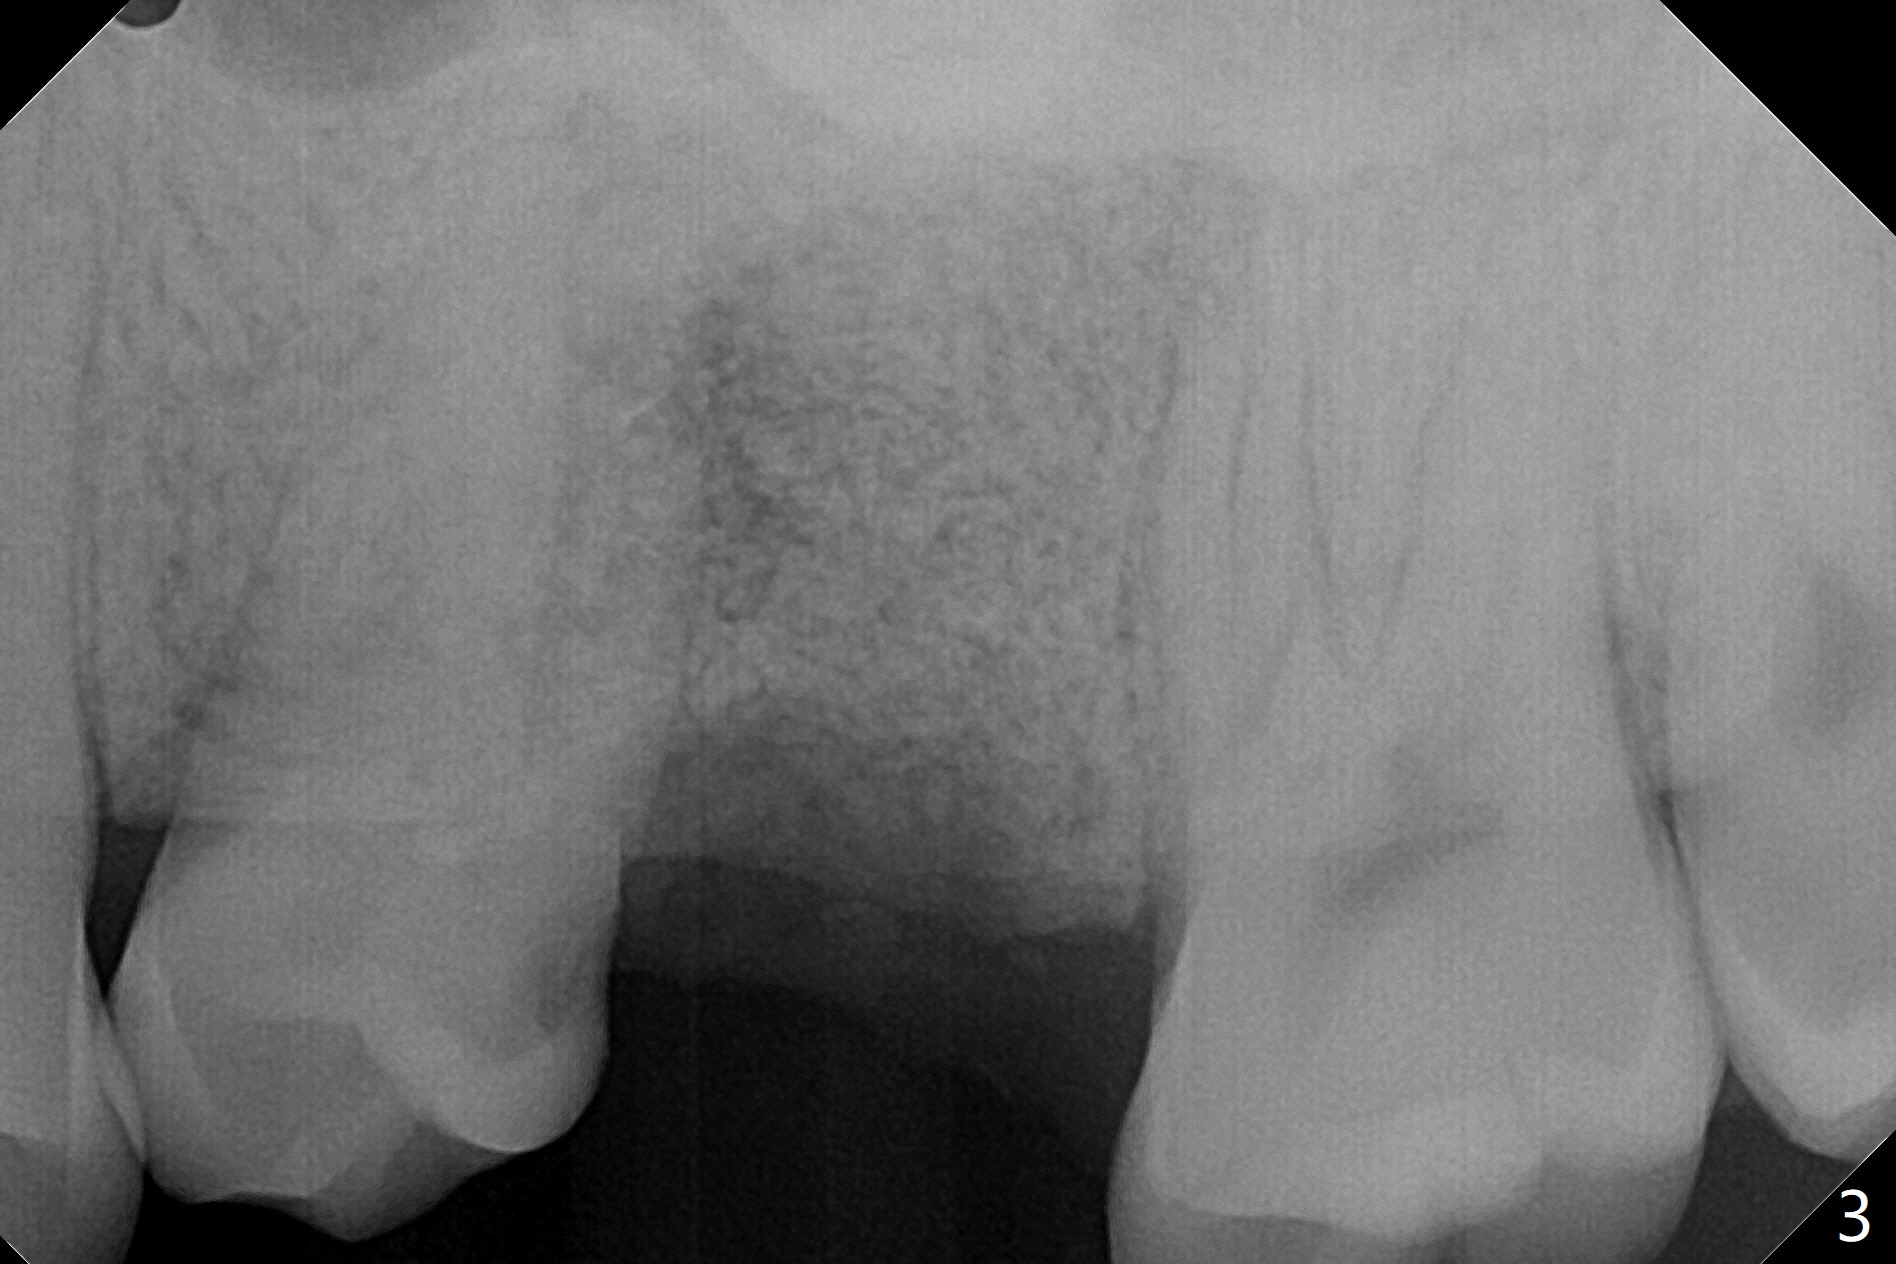

A 29-year-old man has pain in the upper left quadrant. It appears that the tooth #14 has endo and post failure with palatal fistula (Fig.1,2). The septum is almost non-existent; the palatal wall is low, while the sinus floor is present. Sticky bone is placed first against the defective palatal wall and presumably pushed as high as to the sinus floor (Fig.3-5). PRF plug/membrane and 6-month membrane are used to close the socket with 4-0 Chromic gut suture apparently securely, followed by periodontal dressing. Examination of the extracted tooth shows granulation tissue between the roots (Fig.6 *). Underneath the granulation tissue is cement-like material (Fig.7 C). Distal-to-mesial X-ray examination shows possible furcation perforation (Fig.8 *), while mesial-to-distal one the cement-like material in the furca and pulpal chamber as well as MB2 (Fig.9 >). The patient returns 8 days postop, reporting pain reduction, but wants to have #16 extracted. The periodontal dressing is loose, but stuck with 2 sutures underneath. When the dressing is removed, the wound looks normal (Fig.10). In fact the dressing is re-applied. The 6-month membrane has lost 1 month postop. The majority of the socket heals except the palatal (Fig.11 *), as related to the existing palatal fistula/defect (^). Orthodontics is being considered. If the buccal plate collapses 4.5 months post extraction, socket shield should have been done. In fact the buccal plate is robotic, while the bone density is low palatal in CT (Fig.12).